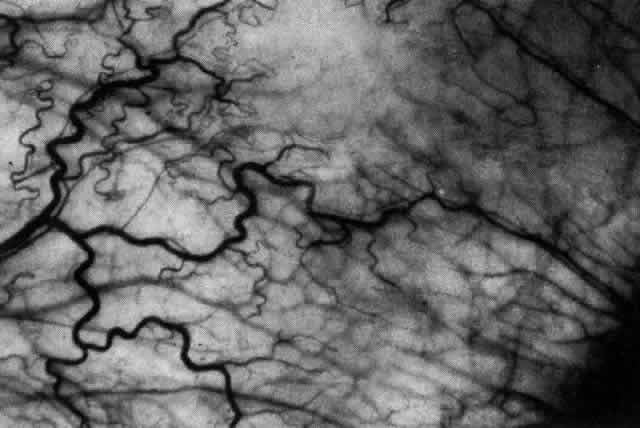

of the eye. A posterior scleritis often occurs as an extension of anterior

disease; but, as in Figure 20, most of the inflammation (in some cases all of the inflammation) is in

the posterior segment and the exudative detachments and subretinal granulomas

Fig. 20. Posterior scleritis. This eye was removed because of loss of vision and

pain, mistakenly diagnosed as malignant melanoma. (Courtesy of Professor N. Ashton) Fig. 20. Posterior scleritis. This eye was removed because of loss of vision and

pain, mistakenly diagnosed as malignant melanoma. (Courtesy of Professor N. Ashton)